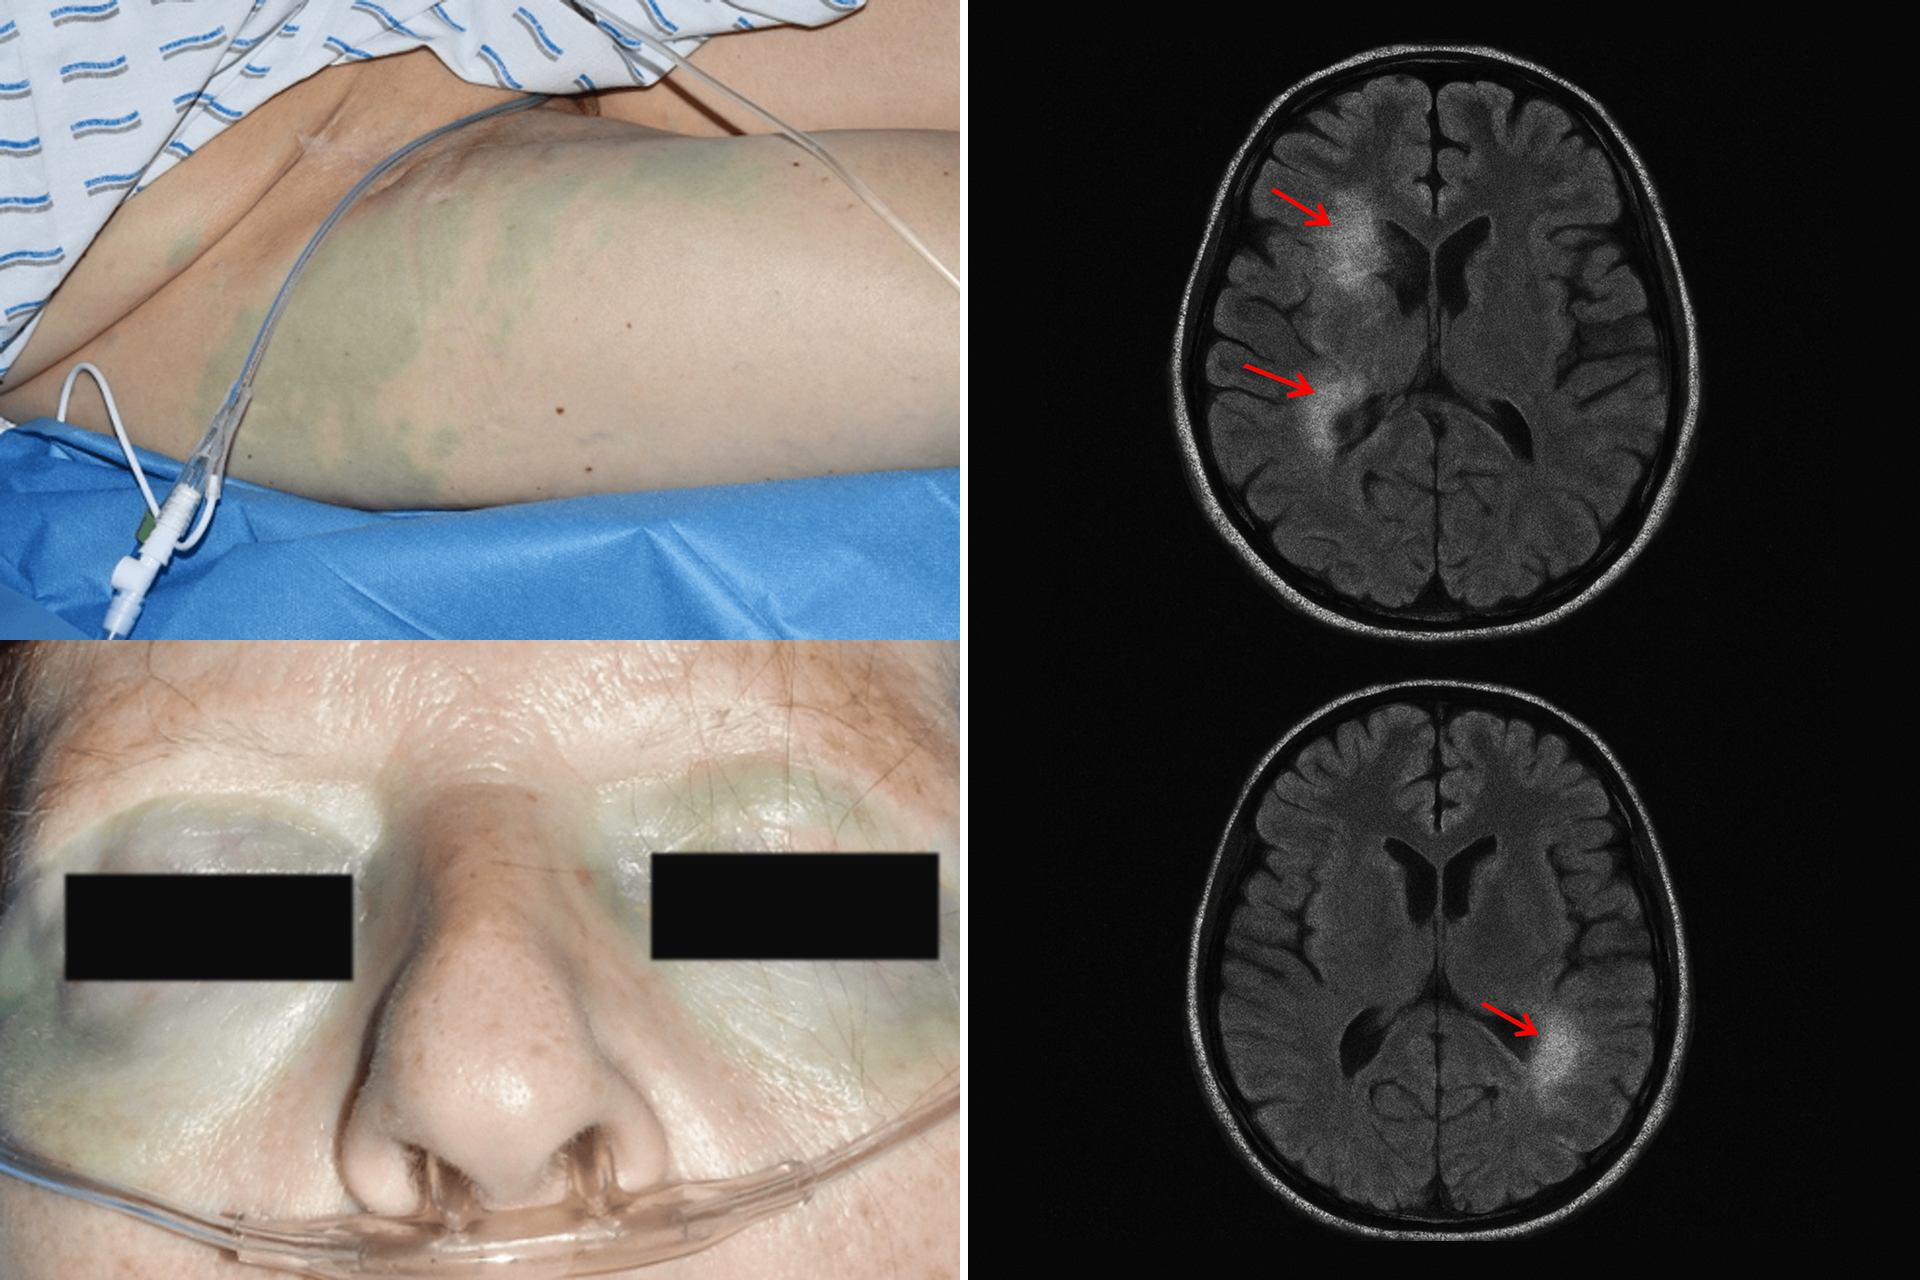

On June 3rd, 2025, A man in Chicago nearly died after taking what he believed was a health supplement. It was Methylene Blue from Amazon. It contained toxic levels of Mercury and Formaldehyde.

Many Methylene Blue products on the market contain hazardous levels of heavy metals, such as lead and mercury, toxins that accumulate in the brain and nervous system over time.

Cheap Methylene Blue products are contaminated with heavy metals (Mercury, Lead, Cadmium) and Formaldehyde

Toxins that accumulate in your brain, liver, and nervous system over time. Unlike other contaminants that your body can flush out, these substances build up with each dose.

Dr. Michael Rodriguez, a neurologist who's treated patients with Methylene Blue toxicity, painted a terrifying picture: "We had a patient who took contaminated Methylene Blue for cognitive enhancement. After six months, his mercury levels were so high that we had to start emergency chelation therapy. The scary part? He felt fine until the day he didn't."